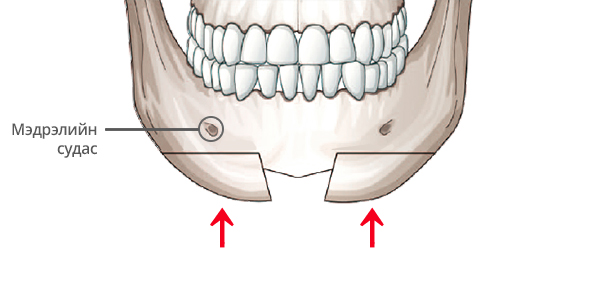

Step 3

Богиноссон эрүүг өргөж, эрүүний гол хэсгийн ясыг зүсэж авна.